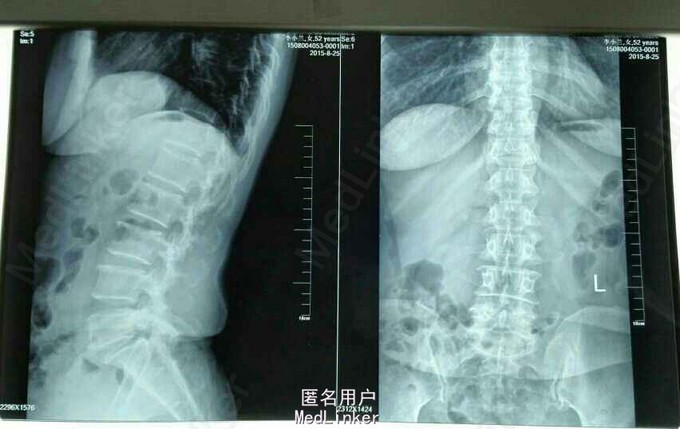

跛行步态,腰椎活动轻度受限,L5棘突及右侧脊旁压痛、叩痛,VAS评分腰痛3分,腿痛2分,JOA评分14分,ODI评分40%,余无明显阳性体征。外院MR提示:L5向前Ⅰ度滑脱并椎弓根峡部崩裂。我院腰椎动力位片示:1.腰椎退行性变,2. L5向前Ⅰ度滑脱并椎弓根峡部崩裂。

52岁女性患者,起病50余天,经保守治疗半月后症状无明显改善,腰椎MR及腰椎动力位片均提示:L5椎体滑脱。行L5/S1椎体融合术,术后患者双下肢麻痛及乏力明显缓解。对于腰椎滑脱的患者,经积极保守治疗后症状无明显改善者,应行手术治疗,手术效果较好。术后1月返院复查并复查腰椎X片。